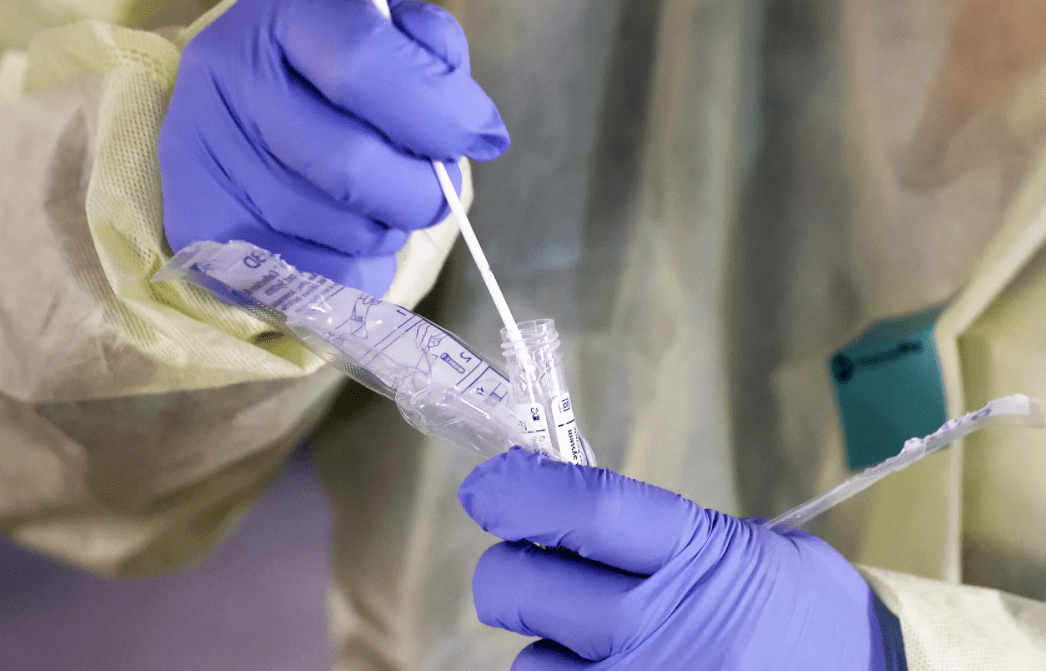

Можно ли точно определить, что уже переболел

На сегодня доступен специальный тест, который можно пройти после предварительной записи. Он бесплатный. Для этого берут анализ крови из вены без какой-либо предварительной подготовки. Вот как можно узнать, что уже переболел коронавирусом и есть антитела. Результат записывается в электронной медицинской карте пациента в течение трех дней от даты сдачи анализа.

Если в анализе будут обнаружены антитела, то человек сможет стать донором плазмы. Она незаменима для людей со средней и сложной формой COVID-19. Благодаря переливанию плазмы удается до 92% увеличить шансы на выздоровление.

Есть ли смысл обращаться в частные лаборатории

На фоне пандемии стала появляться информация о частных лабораториях, которые делают тест на коронавирус. Квалифицированные специалисты утверждают, что в таких учреждениях не дадут точного ответа на вопрос, заразились вы или нет. Проводимые ими тесты могут лишь зафиксировать присутствие генома вируса, то есть то, присутствует ли он в крови в данный момент.

Понять, приходилось ли организму сталкиваться с вирусом когда-либо, с их помощью не удастся. Тесты не смогут этого показать. Указать на перенесенный вирус в прошлом могут иммуноглобулины. Они представляют собой некий «шлейф» перенесенной инфекции. Их формирование происходит в ответ на проникновение инфекции в органы и ткани. Именно их необходимо искать, чтобы определить, переболел определенный человек коронавирусом или нет.